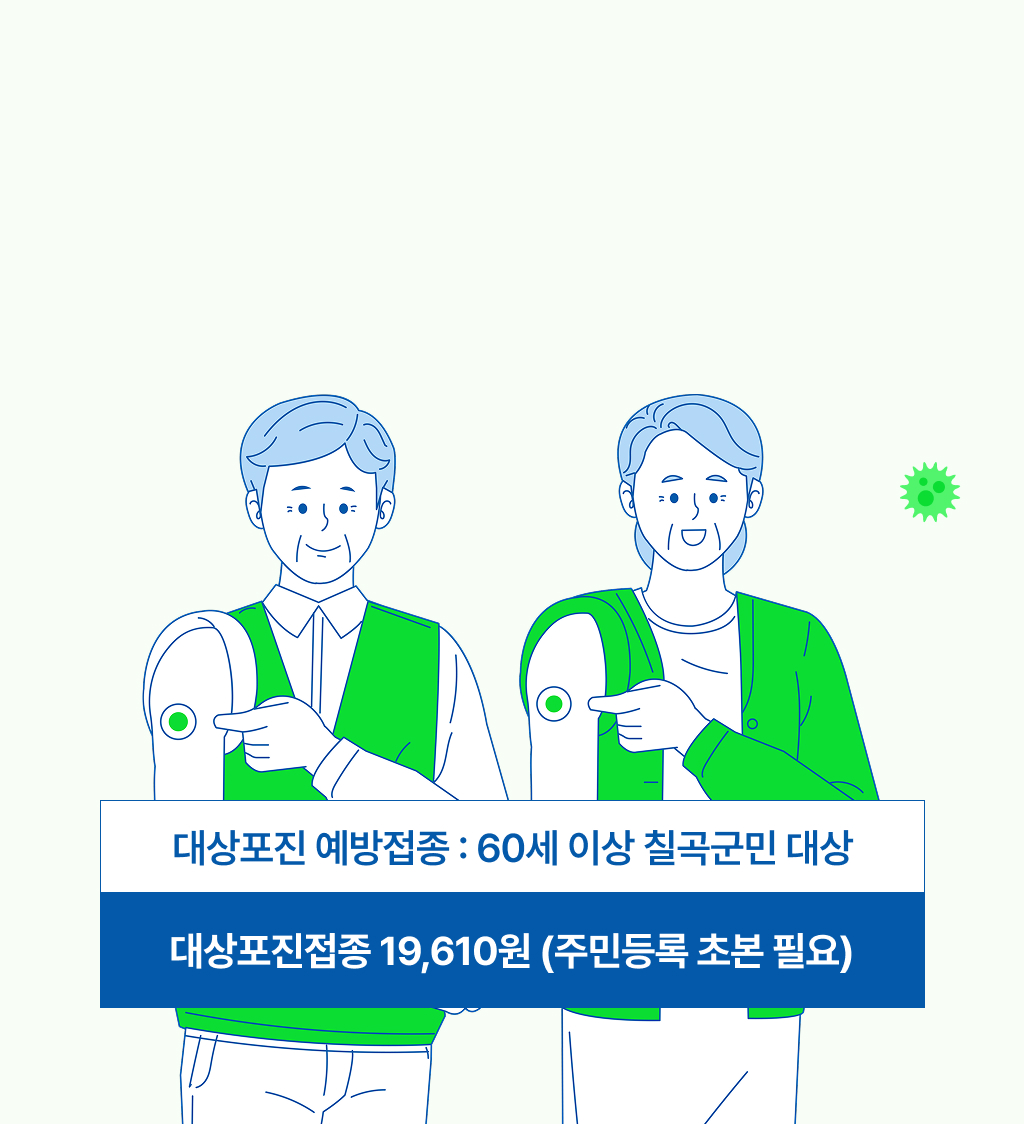

대상포진 예방접종

60세 이상 칠곡군민(1년 이상 거주자)

대상포진은 예방이 가장 중요합니다!

지금 건강을 지켜보세요.